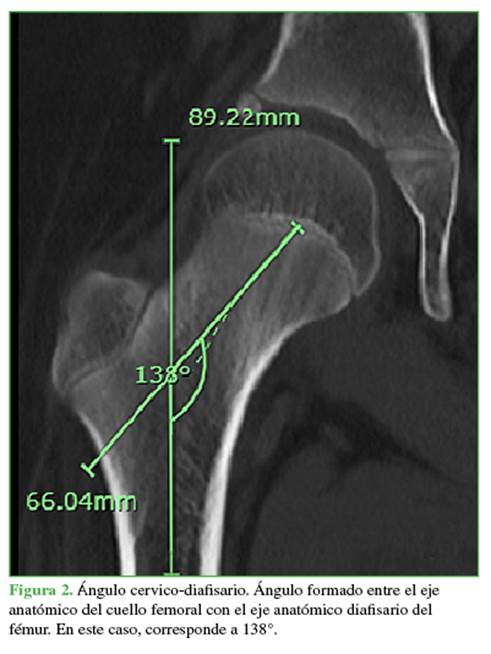

La longitud del cuello corresponde a la distancia desde el centro de la fisis del fémur proximal transcurriendo por el eje del cuello femoral hasta el eje de la diáfisis (Figura 3).

Se incluyó a 40 pacientes (promedio de edad, 9 años; rango de 6 meses a 18 años). El desplazamiento femoral muestra un crecimiento lineal en el tiempo con una tendencia a aumentar aproximadamente 1,96 mm al año hasta los 12.5 años, con un posterior aplanamiento de la curva y un aumento en el desplazamiento de 1,2 mm entre los 12.5 y 16 años (Figura 5). Respecto a la longitud del cuello femoral, la tendencia de crecimiento es constante, a una velocidad de 1,95 mm por año (Figura 6).

En nuestra población, el desplazamiento aumentó con la edad, desde una medida promedio de 20 mm a los 5 años y hasta 37 mm a los 15 años (6 mm y 3 mm menos que la población de Szuper y cols., respectivamente). La longitud del cuello femoral tuvo un promedio de 33 mm a los 5 años y de 49 mm a los 15 años (1 mm y 1,5 mm, respectivamente, inferior a la población de Szuper y cols.). El tamaño de la cabeza femoral también fue menor que en la población comparada, con promedios de 24,6 mm a los 5 años y 38,2 mm a los 15 años (4 mm y 5,5 mm de diferencia, respectivamente). Estos cambios pueden estar relacionados con una talla más baja en nuestra población desde el nacimiento hasta la adultez comparada con la población húngara. La brecha encontrada disminuye progresivamente gracias a una mayor velocidad de incremento del desplazamiento y el tamaño de la cabeza femoral.